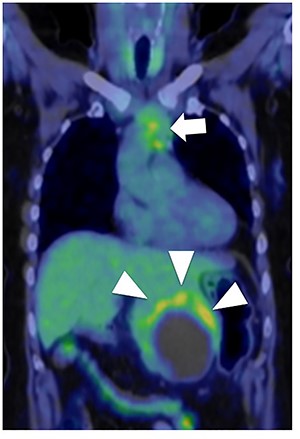

A 56-year-old woman presented to another hospital with acute abdomen. Computed tomography (CT) examination demonstrated a tumor 10 cm in diameter that protruded from the left lateral segment of the liver, with evidence suggestive of rupture of the liver tumor (Fig. 1). Since the patient was in good general condition, she was referred to our hospital for further evaluation. Her blood biochemical parameters when she was referred to our hospital were hemoglobin: 11.6 g/dl, albumin: 3.4 g/dl, γ-globulin: 18.5% and anti-acetylcholine receptor antibody: <0.3 nmol/L. Dynamic CT presented a liver tumor 10 cm in diameter, which was located at the left lateral segment of the liver, with a clear margin. A mass with an irregular margin was also identified in the anterior mediastinum (Fig. 2). On percutaneous angiography, since obvious extravasation of the contrast medium could not be identified, the arteries of the left lateral segment were embolized to prevent re-bleeding. Although a definitive preoperative diagnosis could not be made using magnetic resonance imaging (MRI) (Fig. 3), fluorodeoxyglucose positron emission tomography (FDG) showed increased FDG uptake in both the hepatic and anterior mediastinal tumors (Fig. 4). Although the liver tumor was suspected to be metastasis secondary to a thymoma based on the clinical findings, percutaneous tumor biopsy was performed to confirm the pathological diagnosis. The biopsy suggested malignant T-cell lymphoma or metastatic thymoma. In order to prevent re-rupture of the hepatic tumor, to confirm the pathological diagnosis and to potentially achieve a curative resection, the patient underwent laparoscopic left lateral segmentectomy (Fig. 5). Although the tumor was found to be adherent to the stomach, blunt dissection was possible. In addition, no peritoneal dissemination was detected. The surgical duration was 212 min and estimated blood loss was 50 ml. The liver tumor was pathologically diagnosed as metastatic thymoma type AB (Fig. 6). The patient’s postoperative course was uneventful and she subsequently underwent radical thymectomy 3 months after the liver resection. The thymic tumor was pathologically diagnosed as thymoma type B2. Currently, 30 months after thymectomy, she remains free from tumor recurrence.

Fluorodeoxyglucose positron emission tomography. Maximum standard uptake value of the liver tumor (arrow head) was 4.8 and that of the anterior mediastinal tumor (arrow) was 3.9. Neither lymph node metastasis nor other distant metastasis was detected.